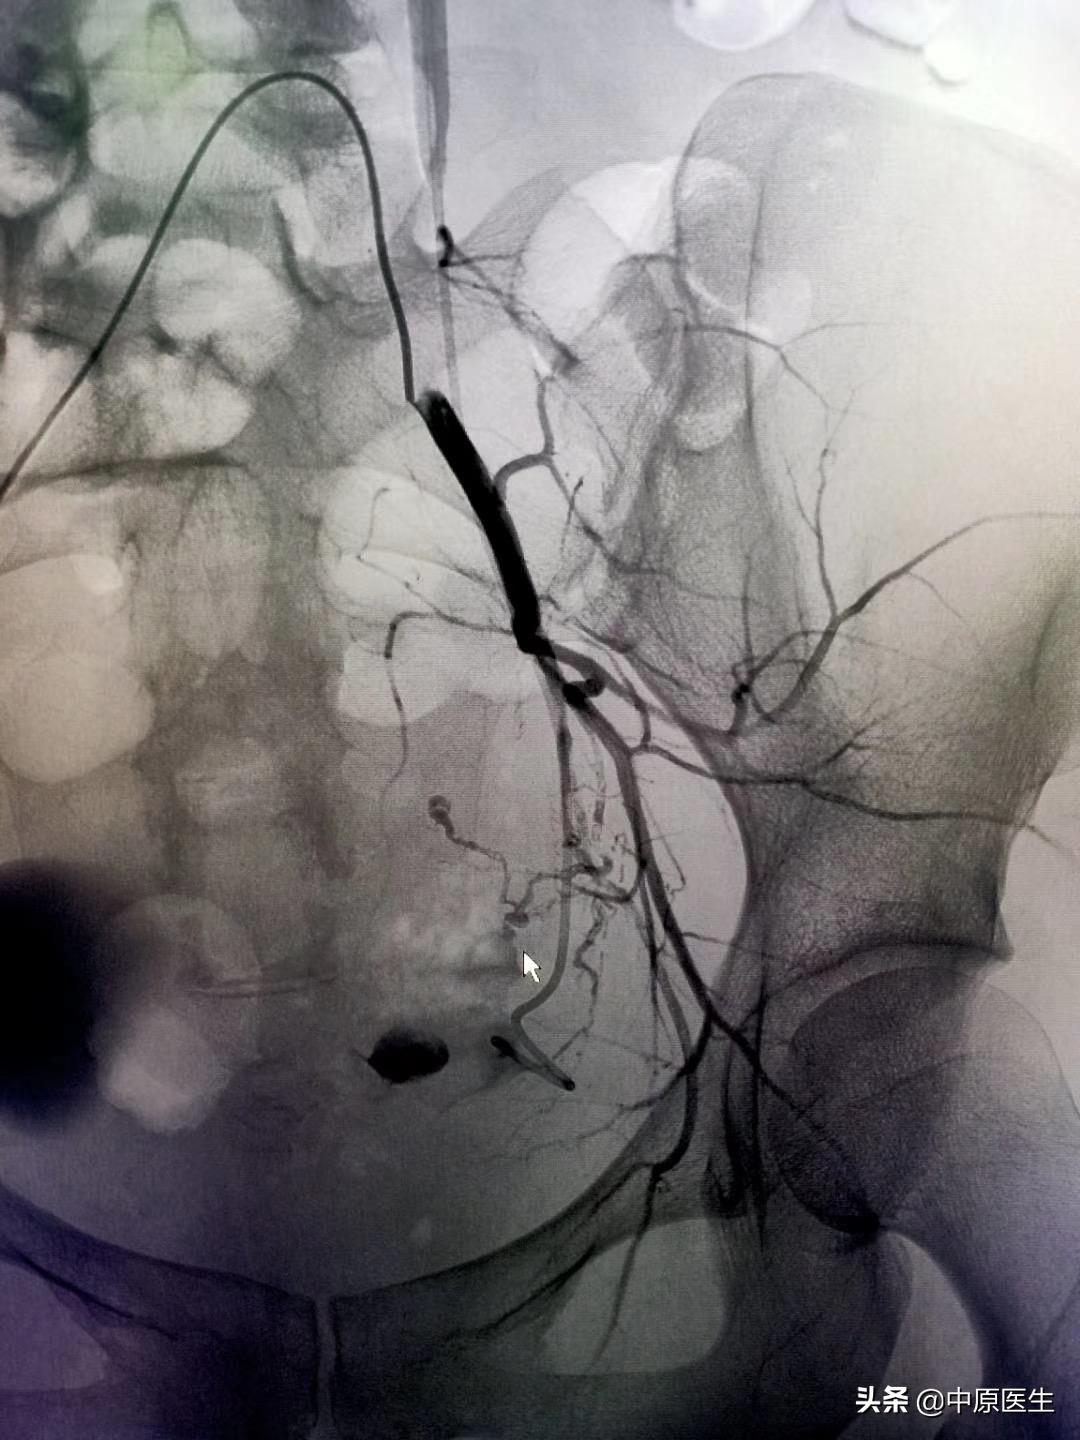

我处理好门诊事宜,十点赶往导管室,按标准预防做好术前防护、术前准备工作。在导管室的护士、技师等积极配合下,手术顺利开展,造影显示左侧子宫动脉近宫颈处有一破口、形成假性动脉瘤,假性动脉瘤破溃,造影剂快速流入宫腔内(相当于找到了河流的决口处);紧急用生物胶栓塞该破口及其远、近端血管(相当于堵住了决口及其上下游,上游流不进来、下游的倒灌不了),复查造影未见造影剂外渗、动脉瘤、静脉早显等异常血管影(成功止血)。然后选择双侧髂内动脉各分支造影未见明显异常血管,再予右侧子宫动脉栓塞。半小时顺利完成手术,病人生命体征平稳。安全送回病房,继续药物治疗。

子宫动脉栓塞术是治疗妇产科疾病常用技术,美国前国务卿赖斯曾因子宫肌瘤行子宫动脉栓塞术。具体操作是在DSA等影像设备引导下,局部麻醉,从大腿根部的股动脉穿刺、约一米粒大小的针眼,送入直径约2mm的导管到达病灶供血动脉,利用栓塞颗粒、微弹簧圈、生物胶等栓塞材料阻断病变的供血血管,达到止血和/或使病变缺少营养,继而坏死、萎缩缩小。DSA的火眼金睛可使出血动脉和肿瘤供血动脉无处可逃,这样的栓塞治疗,具有疗效确切、创伤小、无切口、恢复快、复发率低、可保留子宫的优点,这样的治疗,可以让女人保留原装子宫、做完美的女人!(本号总顾问梁宝松教授,1984年毕业于河南医科大学本科,河南省人民医院消化内科主任医师 教授)